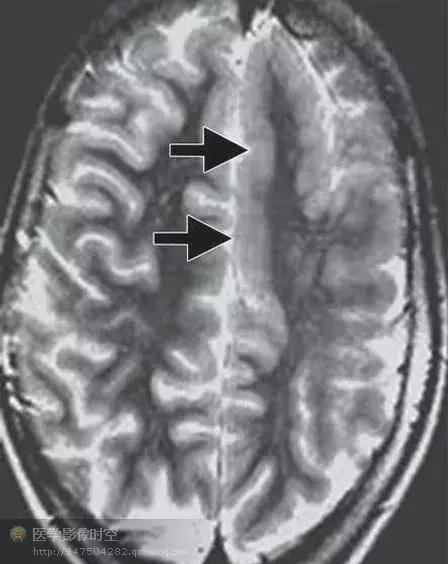

目前的影像学检查方法,包括磁共振成像,磁源成像,或者PET尚不能可靠的鉴别轻度皮质发育不良,局部皮质发育不良Ⅰ型和Ⅱ型(图1-6)。但是,如果发现皮层下T2高信号,尤其是延伸到侧脑室,常常是ⅡB型(图2)。目前认为T2高信号是髓鞘化程度低造成的,而非气球样细胞所致。其它的局部皮质发育不良的典型磁共振成像表现包括局部皮质增厚,灰白质界限模糊,灰质高信号(图6)。

图6 局部皮质发育不良

图6a横断T2WI显示灰质增厚(箭)

图6b冠状T2WI显示灰白质交界区模糊(箭).

图6c d横断T2WI显示灰质高信号(图c)和白质高信号(图d)